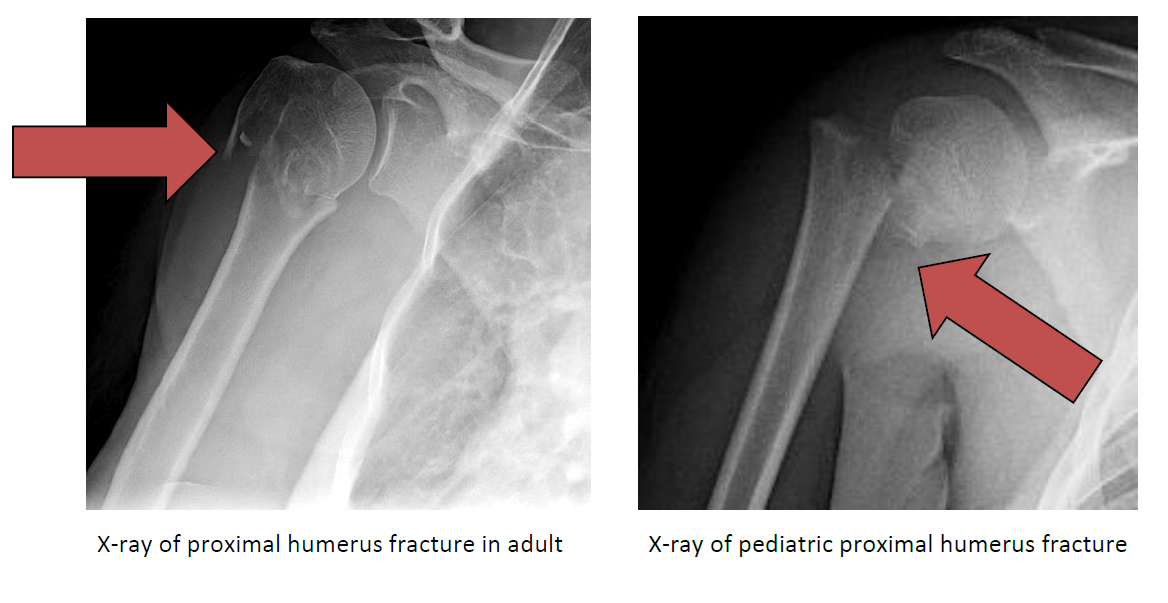

A fracture to the humerus bone is a possible consequence of a traumatic event, such as a fall or forceful collision. Try to do this every 1 to 2 hours for the next 3 days (when you are awake). Only use an ice pack on areas that have normal skin sensation i.e. Symptoms of a broken humerus. Try to do this every 1 to 2 hours for the next 3 days (when you are awake). Put ice or a cold pack on your arm for 10 to 20 minutes at a time. Not apply an ice pack to an area that has poor. Where you can feel hot and cold. A proximal humerus fracture is a serious injury to the humerus bone in the shoulder joint that requires immediate treatment to preserve function of the shoulder. When should heat or ice be applied to the area of a broken bone?